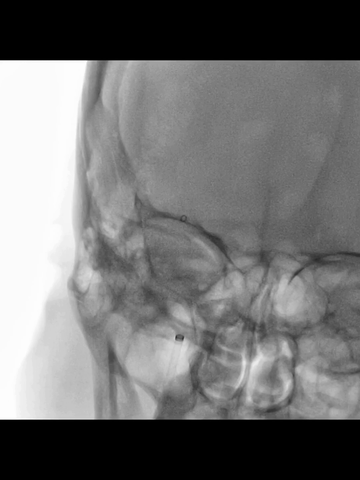

6F中间管先送至长鞘头端,而后在微导管(Rebar 18)微导丝(synchro)引导下进入海绵窦段,而后微导丝越过虹吸段进入MCA近端。

正位透视下,微导管配合,微导丝超选进入M2,侧位透视导丝符合下干走形后,微导管跟进到下干远段,造影确认位于真腔。

鉴于术前CT提示血栓范围长和负荷大,故于微导管送入一长取栓支架(4*40mm),争取一次取栓成功;支架释放后造影见:闭塞段少许前向血流,证实取栓支架已覆盖长段血栓,支架远端超出血栓远端一段较长距离。